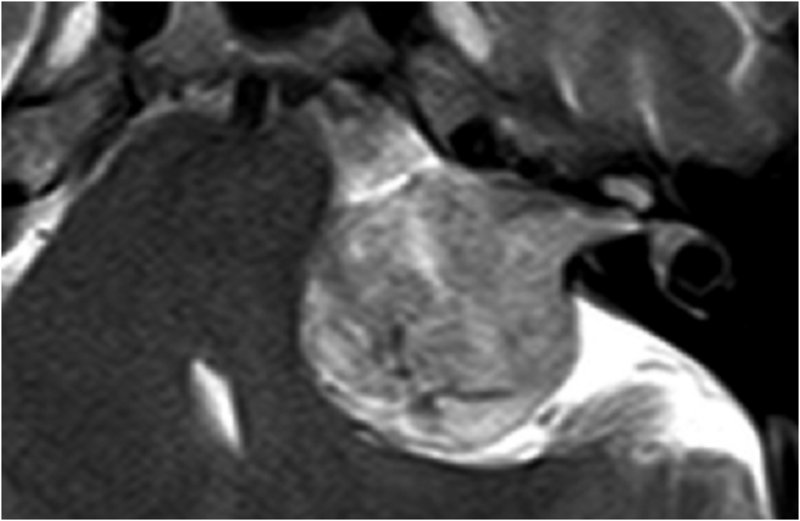

Akustikusneurinom T2 - axial - Vergrößerung

Akustikusneurinom mit typischem "Eistüten"-Bild.